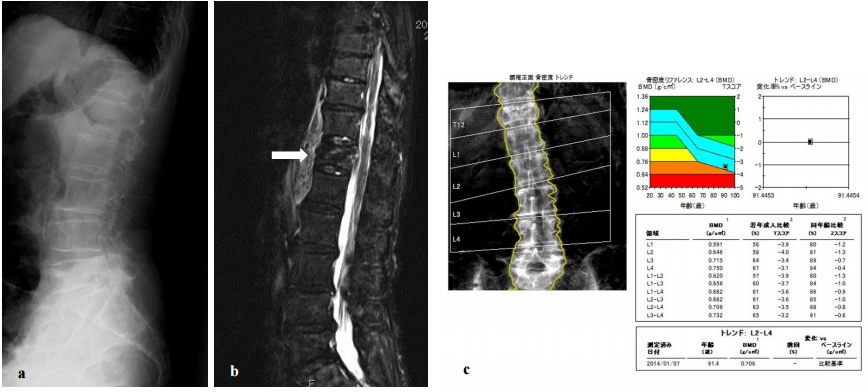

図2. 73歳女性、第12胸椎および第1腰椎骨折手術例

転倒により受傷、他院で保存治療を行うも両下肢麻痺出現し手術目的に紹介された。

MRIでは、第12胸椎および第1腰椎骨折により脊髄が圧迫されていた(a)。

椎体形成術および胸腰椎後方固定術を行い(b)、麻痺が改善し自立歩行可能となった。

腰椎DXAでは高度骨粗鬆症であり(c)、術後はビスホスホネート製剤による骨粗鬆症治療を継続中である。